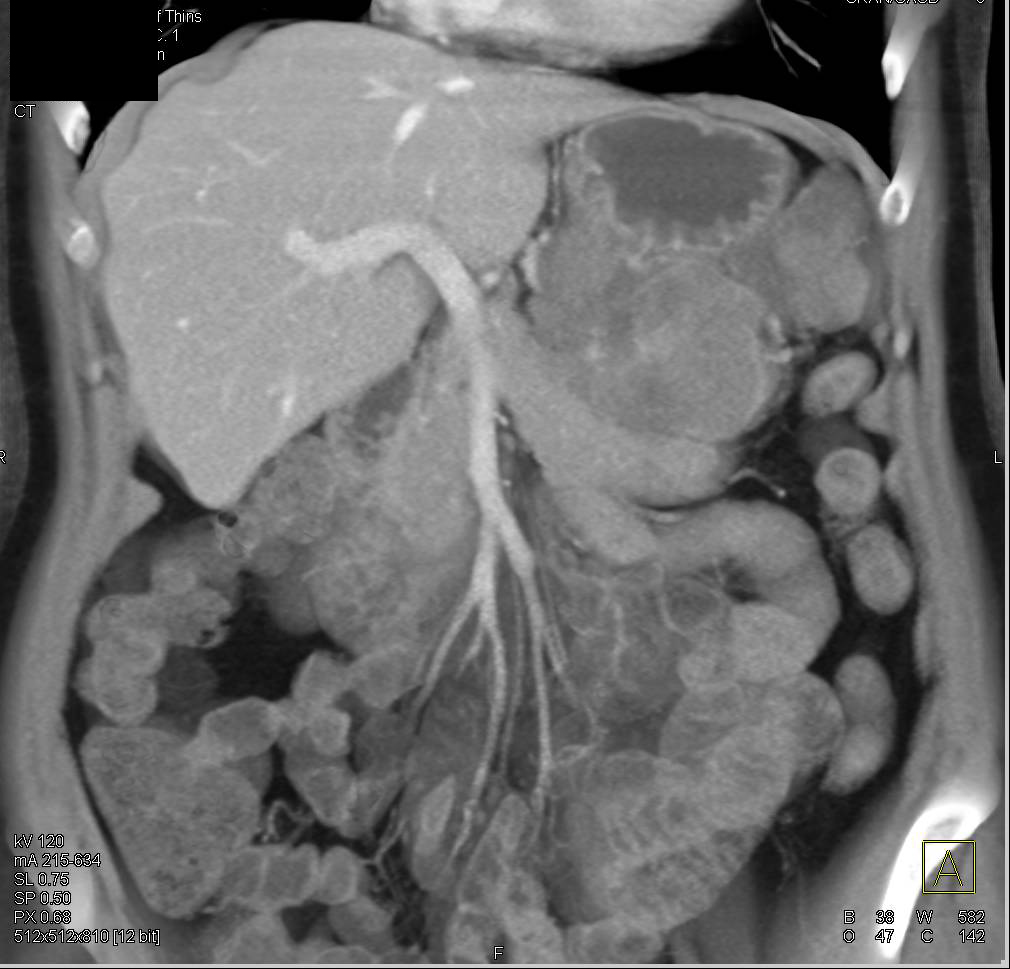

Pancreatic Cancer Causes Gastric Outlet Obstruction